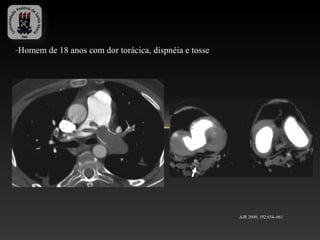

-Homem de 18 anos com dor torácica, dispnéia e tosse

AJR 2009; 192:654–661